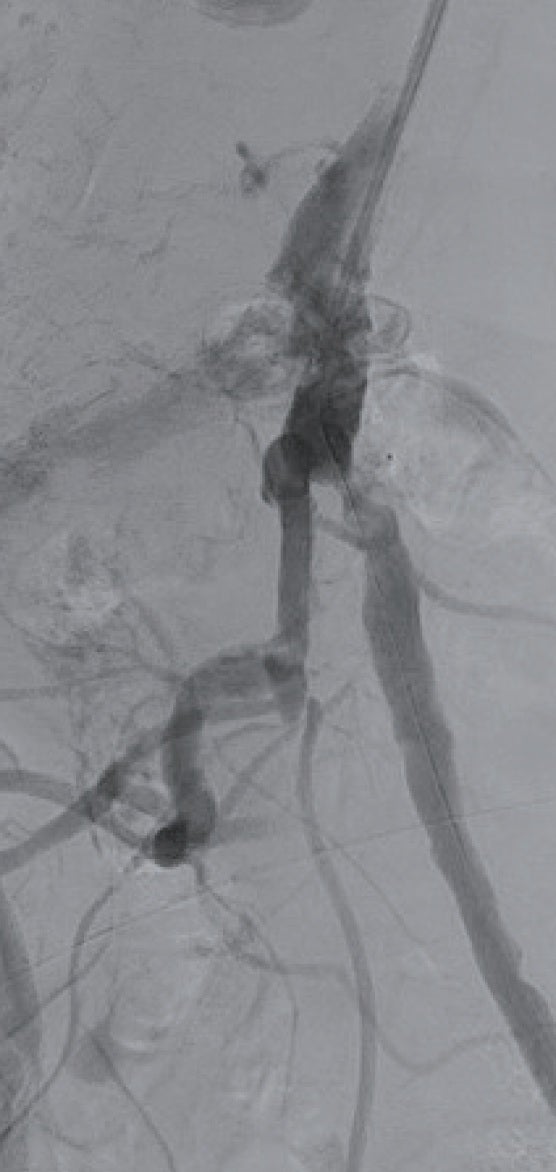

最終造影画像

6 Frガイディングシースに変更しガイディングシースを左総腸骨動脈まで進めた。ガイドワイヤー通過は困難であったが、何とか0.014 inchガイドワイヤーを通過させて(図1b)、小径のバルーンで拡張後、IVUSで病変を評価した(図2)。全周性の表在型石灰化病変であり、通常のベアメタルステントでは拡張できないことが想定され、また内腸骨動脈との分岐部直下に置けるため、ステントグラフトの適応と判断した。6.0 × 40 mmのバルーンで拡張後、6 Frシステム対応のVBX ステントグラフト7.0 × 39 mmを留置、8.0 × 40 mmのバルーンで後拡張を実施(図3)した。IVUSで十分な血管内腔の確保を確認し(図4)、最終造影を行い、治療を終了した。穿刺からシース抜去までの手技時間は38分で、患者は車椅子で退室し、ベッド上の安静時間はゼロであった。足関節上腕血圧比(ABI)は術前の0.70から1.02まで上昇した。